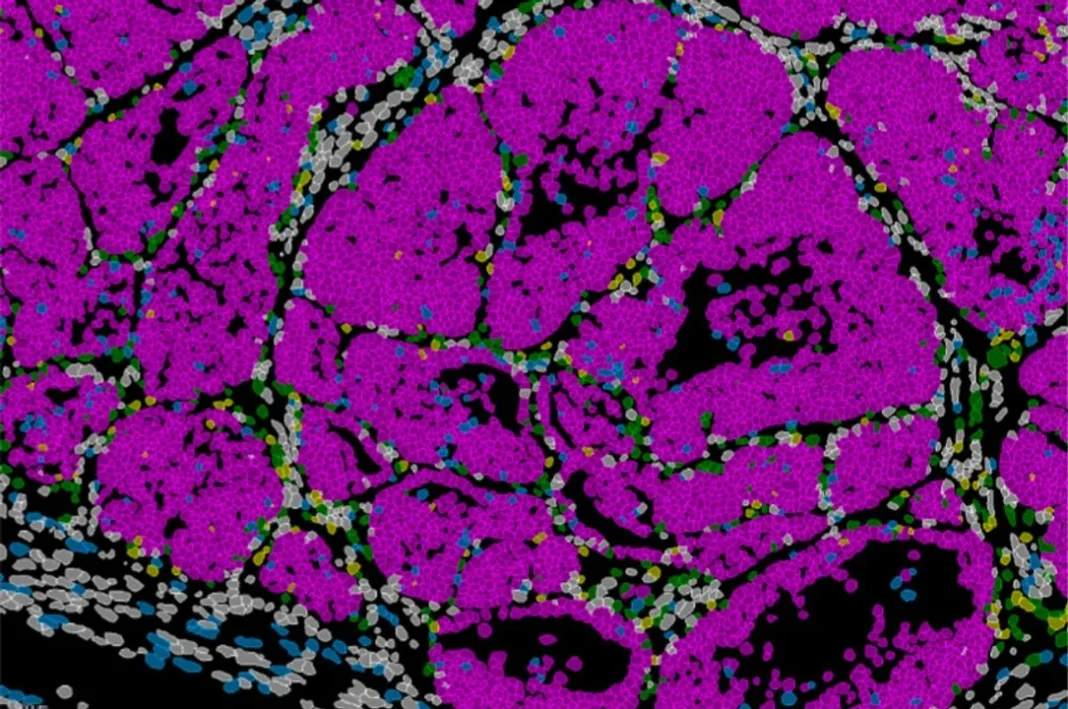

El trabajo, publicado en la revista Nature Communications, se basó en un modelo de ratón y en datos de pacientes. Los científicos identificaron una población de células en el borde invasivo del tumor con capacidad para invadir y dividirse o, alternativamente, entrar en un estado de letargo. El gen Prrx1 es el encargado de regular este equilibrio, que finalmente determina la formación de nuevos focos tumorales en otros órganos.

El equipo combinó modelos genéticos en ratón, análisis de célula única, estudios de cromatina y técnicas de transcriptómica espacial para observar el comportamiento celular directamente en el tejido tumoral. Al analizar muestras de pacientes con cáncer de mama, detectaron patrones similares de expresión del gen Prrx1, lo que sugiere que este mecanismo podría tener relevancia directa en la clasificación y el pronóstico clínico.